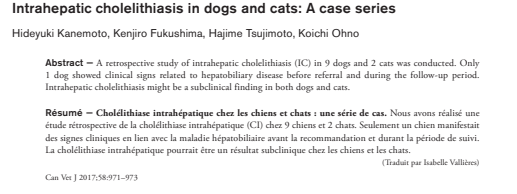

관찰된 담석에 관해 논문에서 다음과 같이 서술하고 있습니다.

간 내부 담석증을 앓고 있는 9마리의 개와 2마리의 고양이로, 1마리의 개만으로 추적관찰 기간에 임상증상을 보였다. 간 내부의 담석증은 준임상적으로 발견될 수 있다.대부분 임상 증상이 발현되지 않고 유지되는 것으로 알려져 있습니다.